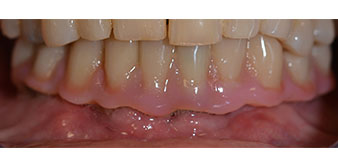

Nach der Zeit, die für die Osseointegration benötigt wird, kann die endgültige Abformung der Implantate erfolgen und entsprechend die endgültige Arbeit angefertigt werden (Abb. 19 und 20). Hier können Behandler und Patient gemeinsam entscheiden, ob diese eine Keramik- oder Kunststoffverblendung, ein Zirkon- oder Metallgerüst bekommen soll. Im vorliegenden Fall hat sich das Team um Dr. Pascu, aufgrund der unklaren Prognose der Oberkieferbezahnung und des elongierten Zahnes 24, für eine Kunststoffverblendung entschieden. Diese ist im Allgemeinen wesentlich einfacher umzustellen und der neuen Situation im Oberkiefer anzupassen.